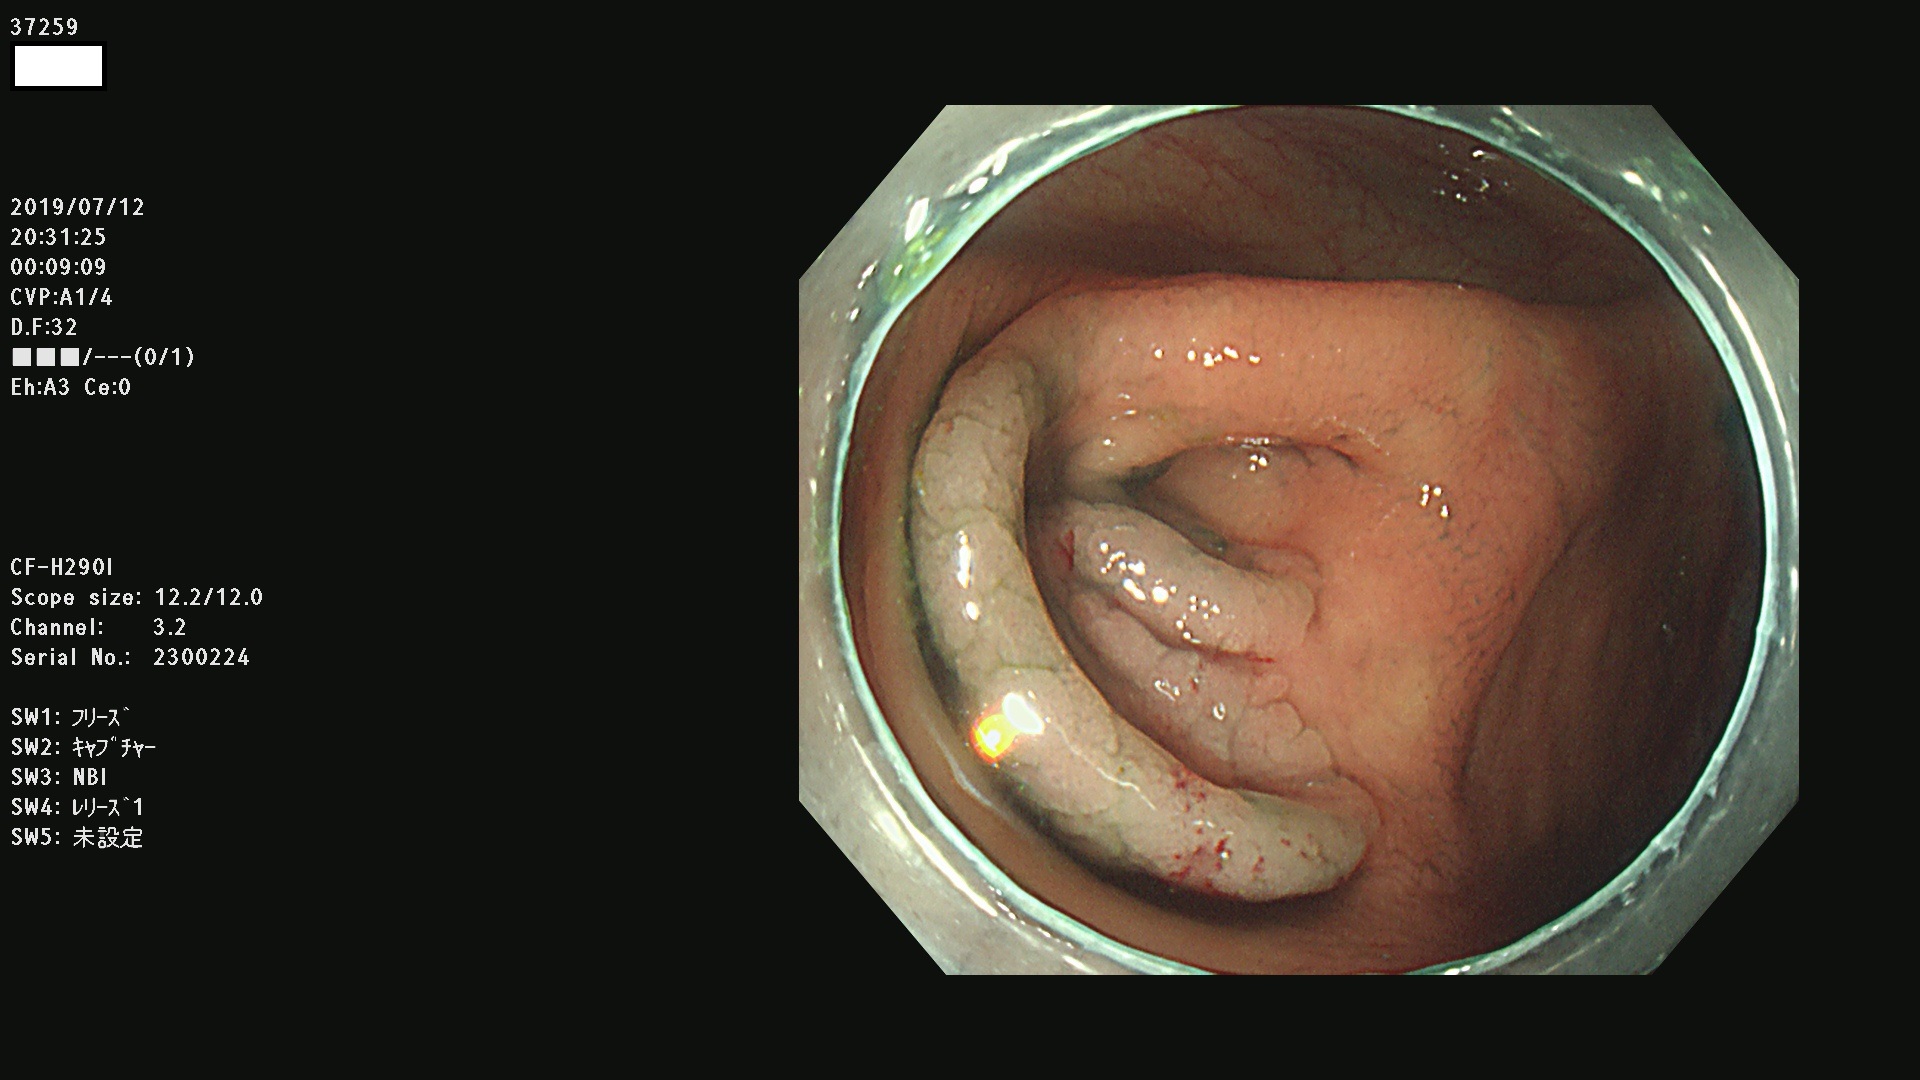

37200 37203 37204 37207 37208 37209 37210 37211 37212 37213 37214 37215 37216 37217 37220 37221 37222 37224 37225 37228 37229 37230 37232 37233 37234 37235 37236 37238 37241 37242 37243 37244 37245(SSAPのみ) 37247 37249 37250 37251 37252(SSAPのみ) 37254 37256 37257 37258 37259 37260(SSAPのみ) 37261(SSAPのみ) 37262 37263 37264 37265 37266 37267 37268(SSAPのみ) 37269 37271 37273 37274 37276 37277 37278 37279 37280 37281 37282 37284(SSAPのみ) 37285 37286 37288 37289 37290 37292 37293 37295 37296 37297(SSAPのみ)

発見困難で危険性の高い平坦型病変(上記100名より抽出)